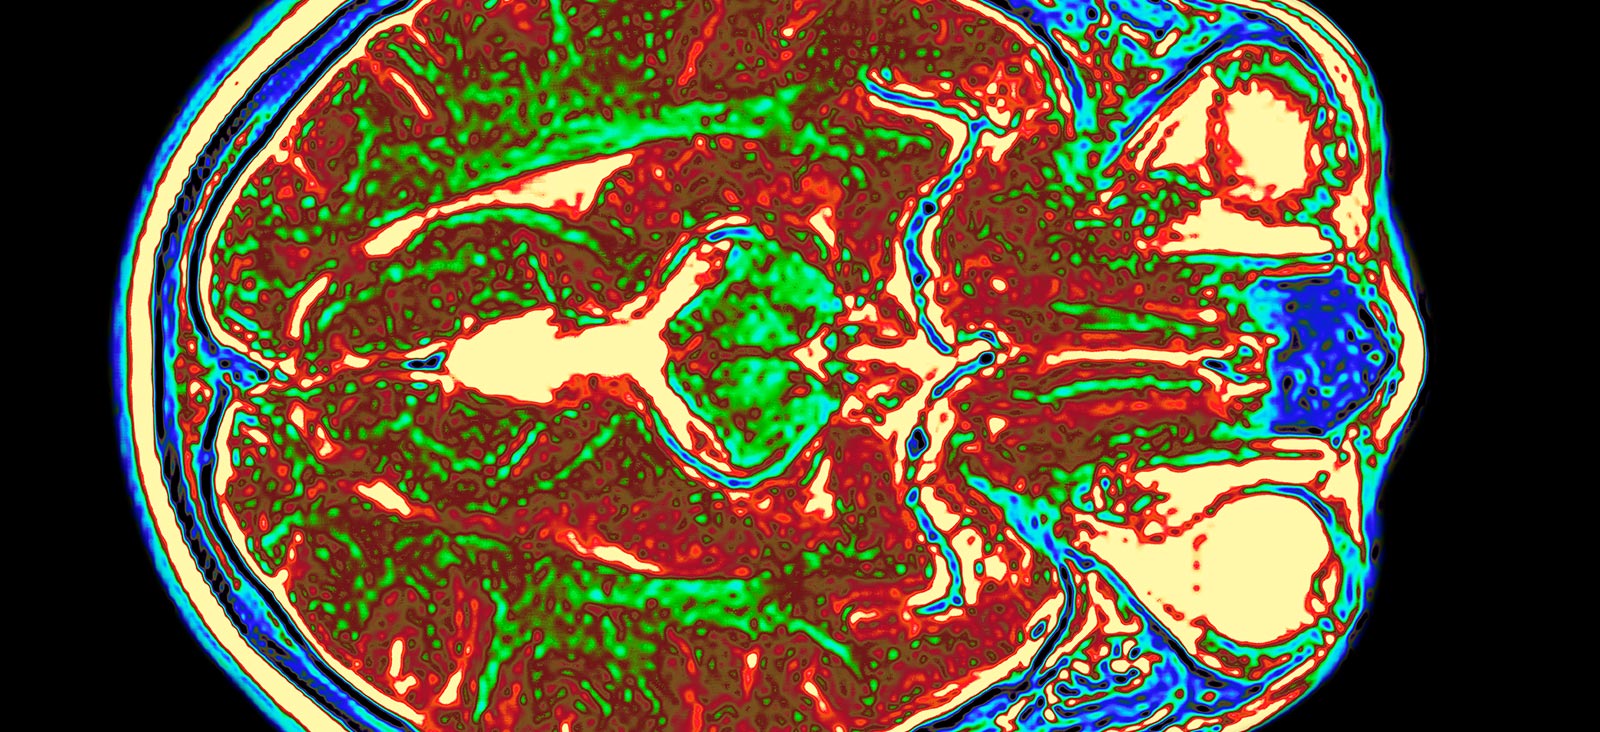

Positron-emission tomography (PET) uses small amounts of radioactive medicine (radiopharmaceuticals) to produce detailed images of structures in the body.

Our dedicated nuclear medicine physicians interpret the images and functional information to identify diseases and conditions earlier and more accurately than other radiological exams, providing patients and physicians better treatment and planning options.

PET/CT can be used to conduct whole-body scans or organ scans for the early detection of cancer or to diagnose a variety of neurological and psychiatric conditions.